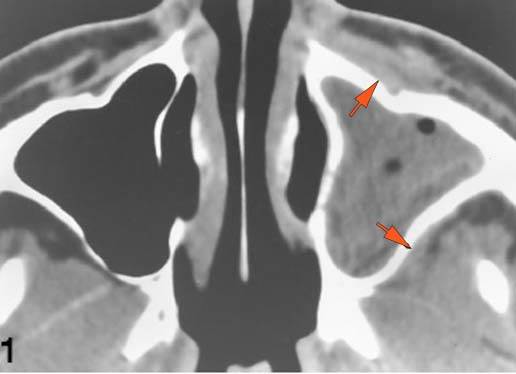

Nasal Cavity and Nasolacrimal Drainage System

There is mucoperiosteal thickening in the nasal cavity.

There is mucosal thickening of the posterior lateral walls of the nasal cavity, cribriform plate or the face of the sphenoid bone.

There is infiltration of soft tissues or bone erosion along the nasolacrimal fossa or canal.